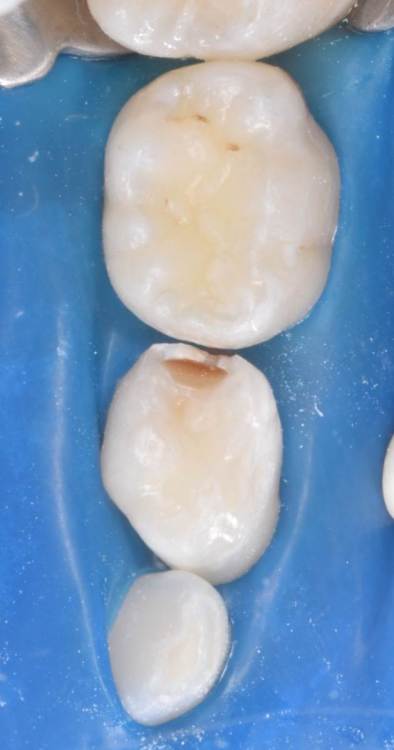

CRAZYDUCK Опубликовано 28 июня, 2022 Автор Поделиться Опубликовано 28 июня, 2022 Ладно , только по снимку нельзя установить диагноз . нет в 6.5 кариозных полостей . только нерентгенконтрастная пломба из градиа , которую я поставила двумя годами ранее . Вот оно как было ДО 3 1 Ссылка на комментарий